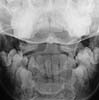

Odontoid